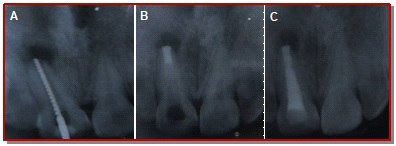

In the present study, the ability of mineral trioxide aggregate in the formation of apical plug for healing of large periapical lesion with open apex was assessed and evaluated the clinical outcome. Fifteen participants with periapical lesion at the upper anterior teeth with open apex were treated with mineral trioxide aggregate. The effect on healing of apical size was evaluated at 3, 6, and 12 months by radiological examinations in the form of periapical index criteria, diameter of the lesion size and the presence or absence of apical tissue barrier. The results found that neither pain nor any sinus was detected at 12 months. The mean size of the apical lesion was gradually reduced from 5.1 × 3.8 to 1.5 × 0.9 mm and mean PAI was reduced from 3.3 to 1.7 mm. The differences between mean size of periapical lesion at preoperative and 12 months observation period was also statistically significant (p<0.05). The clinical success shown significant success rate of 93.3% analyzed with Z-test. In conclusion, tooth with open apex can be successfully treated with mineral trioxide aggregate apexification technique followed by root canal obturation.